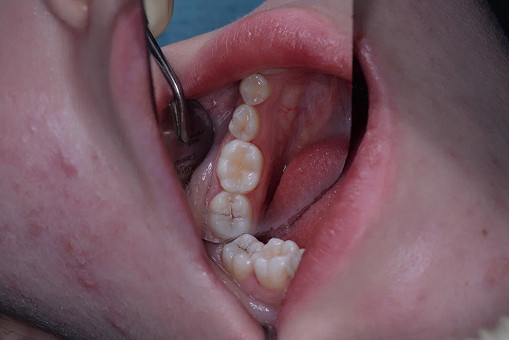

Лечение кариеса проводится следующим образом - сбор анамнеза, проведение местной анестезии, дентальный снимок (при необходимости), изоляция (коффердам), фотопротокол, удаление кариозных тканей (с использованием бора), антисептическая обработка полости, реставрация пломбировочным материалом, шлифовка, полировка.

До/после лечения